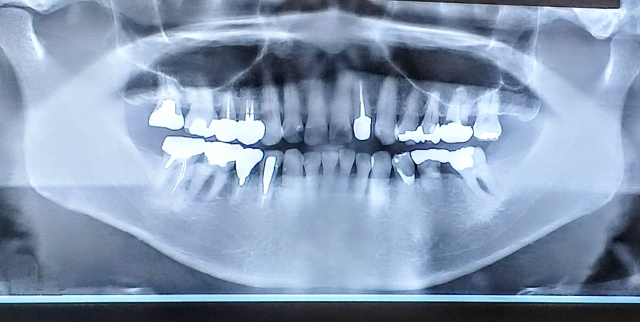

歯の根っこはそれぞれ違うので、本数や形によっても難易度が変わります

例えば前歯は根管が1本ですが大臼歯と呼ばれる奥歯は根管が何本もあります

また、根管の形が曲がっていたり、枝分かれしている歯もあります

そういった歯には器具が入りにくく、1回では根管内の神経を全て除去するのは難しいのです